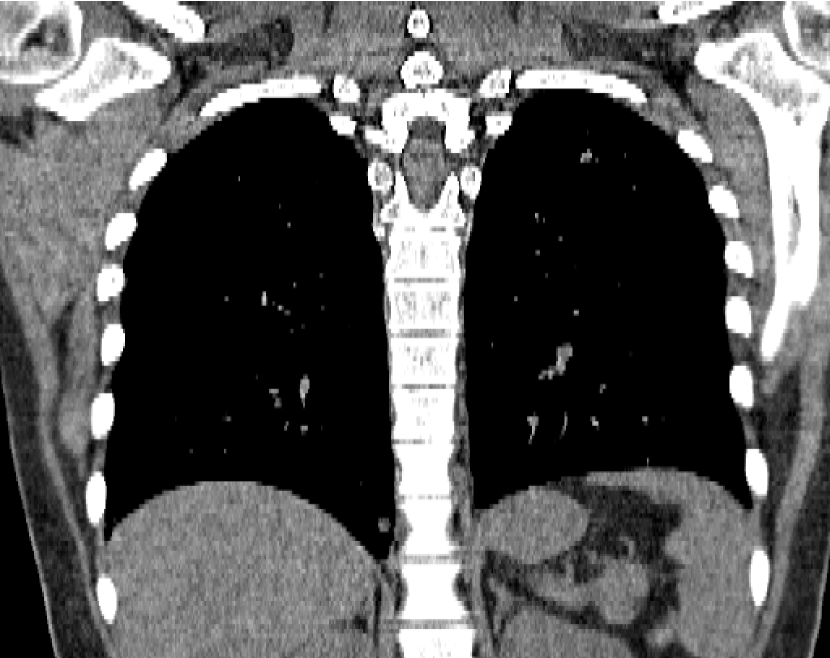

Figure 14: Qualitative clinical results from a thoracic CT staging dataset for a 12-year-old with osteosarcoma with pulmonary metastases. The clinical standard hybrid IR is shown on the left and JENG is on the right. (a) The clinical standard hybrid IR in lung window with a window center of -600 HU and a window width of 1500 HU. (b) JENG at a resolution comparable to the clinical standard, but with less noise and fewer artifacts. (c) The clinical standard hybrid IR in soft tissue window with a window center of 55 HU and a window width of 440 HU. A metastatic lung cancer nodule can be found in the left upper lobe. (d) JENG in soft tissue window at a comparable resolution, but with less noise and fewer artifacts. Note that JENG is not fully corrected for beam hardening artifacts.

Figure 15: An example cross-plane image from the same thoracic dataset as in Fig. 14. (a) A coronal-view image slice of the clinical standard hybrid IR in soft tissue window. (b) JENG at a comparable resolution but with reduced image noise and artifacts.